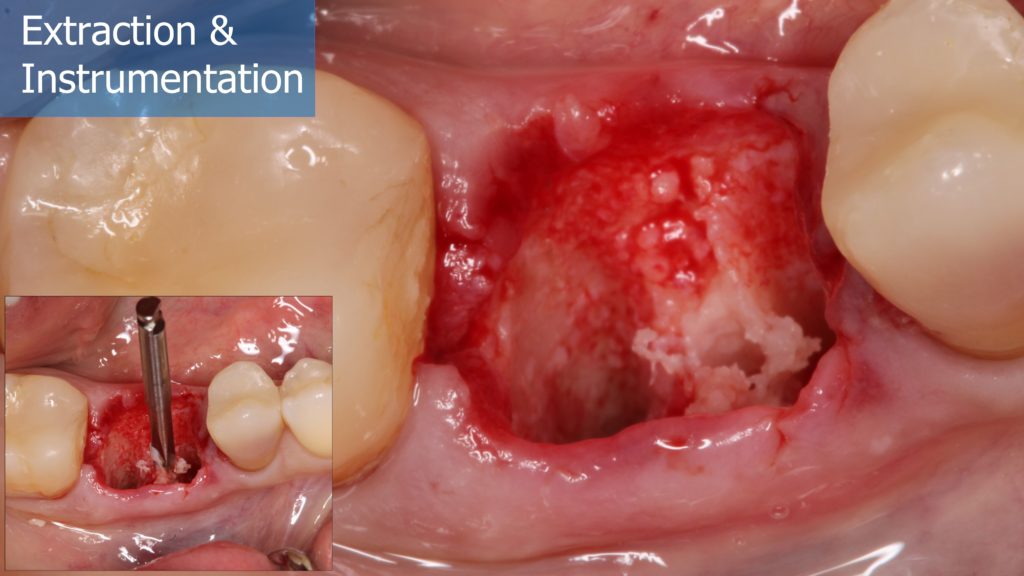

6-12 Months, Augma Bone Cement Academy, Bone Cement Expert, Clinical Cases, Clinical Indication, Clinician, Collagen Sponge/Plug, Coverage Used, Dental Notation, Images, Immediate Placement, Lower Left Molar, Media, Post-Op Period, Socket Grafting, Wound Dressing

Immediate Posterior Implant with Bone Graft

A healthy 36 year old woman comes to the clinic with pain and swelling in the area of the inferior left molars. In the intraoral observation, a vestibular fistula was identified, and the complementary exams confirmed a bone lesion caused by a root perforation (poorly executed false post) on the first lower left molar #36 (19). It was decided to do antibiotic therapy for a week and then the tooth extraction with immediate implant placement and bone graft. 4 months post-op the definitive zirconia/ceramic crown would be was made.